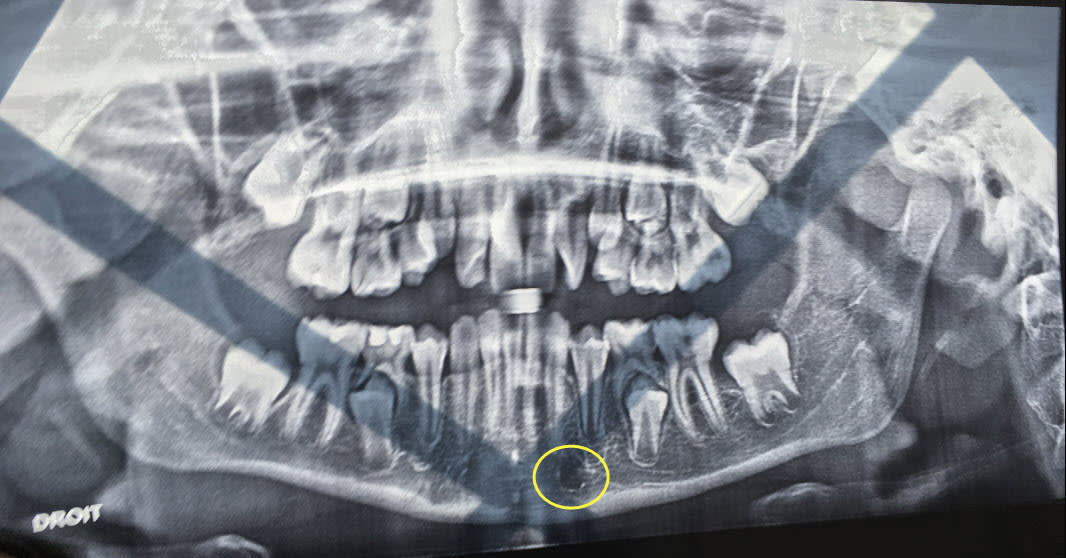

D'ordinaire, les agénésies incisives inférieures, c'est plutôt 31 ou 41 ou plus souvent souvent les 2.

C'est quoi ce truc sur la pano, un artéfact ?

Ce doit être un reflet de sa fenêtre sur l’écran de son ordi lors de de la photo.

Un reflet de fenêtre, ça ne ressemble pas à ça…

Par contre, regardez la différence de taille des couronnes des secondes molaires temporaires par rapport aux deuxième prémolaires. Cela donne de la marge supplémentaire à l'orthodontiste pour éviter des extractions.

Gabzou

21/06/2019 à 10h38

C'est pas tout simplement le foramen mentonnier sur la radio? Vrai qu'il semble un peu en avant mais c'est à çà que çà me fait penser!